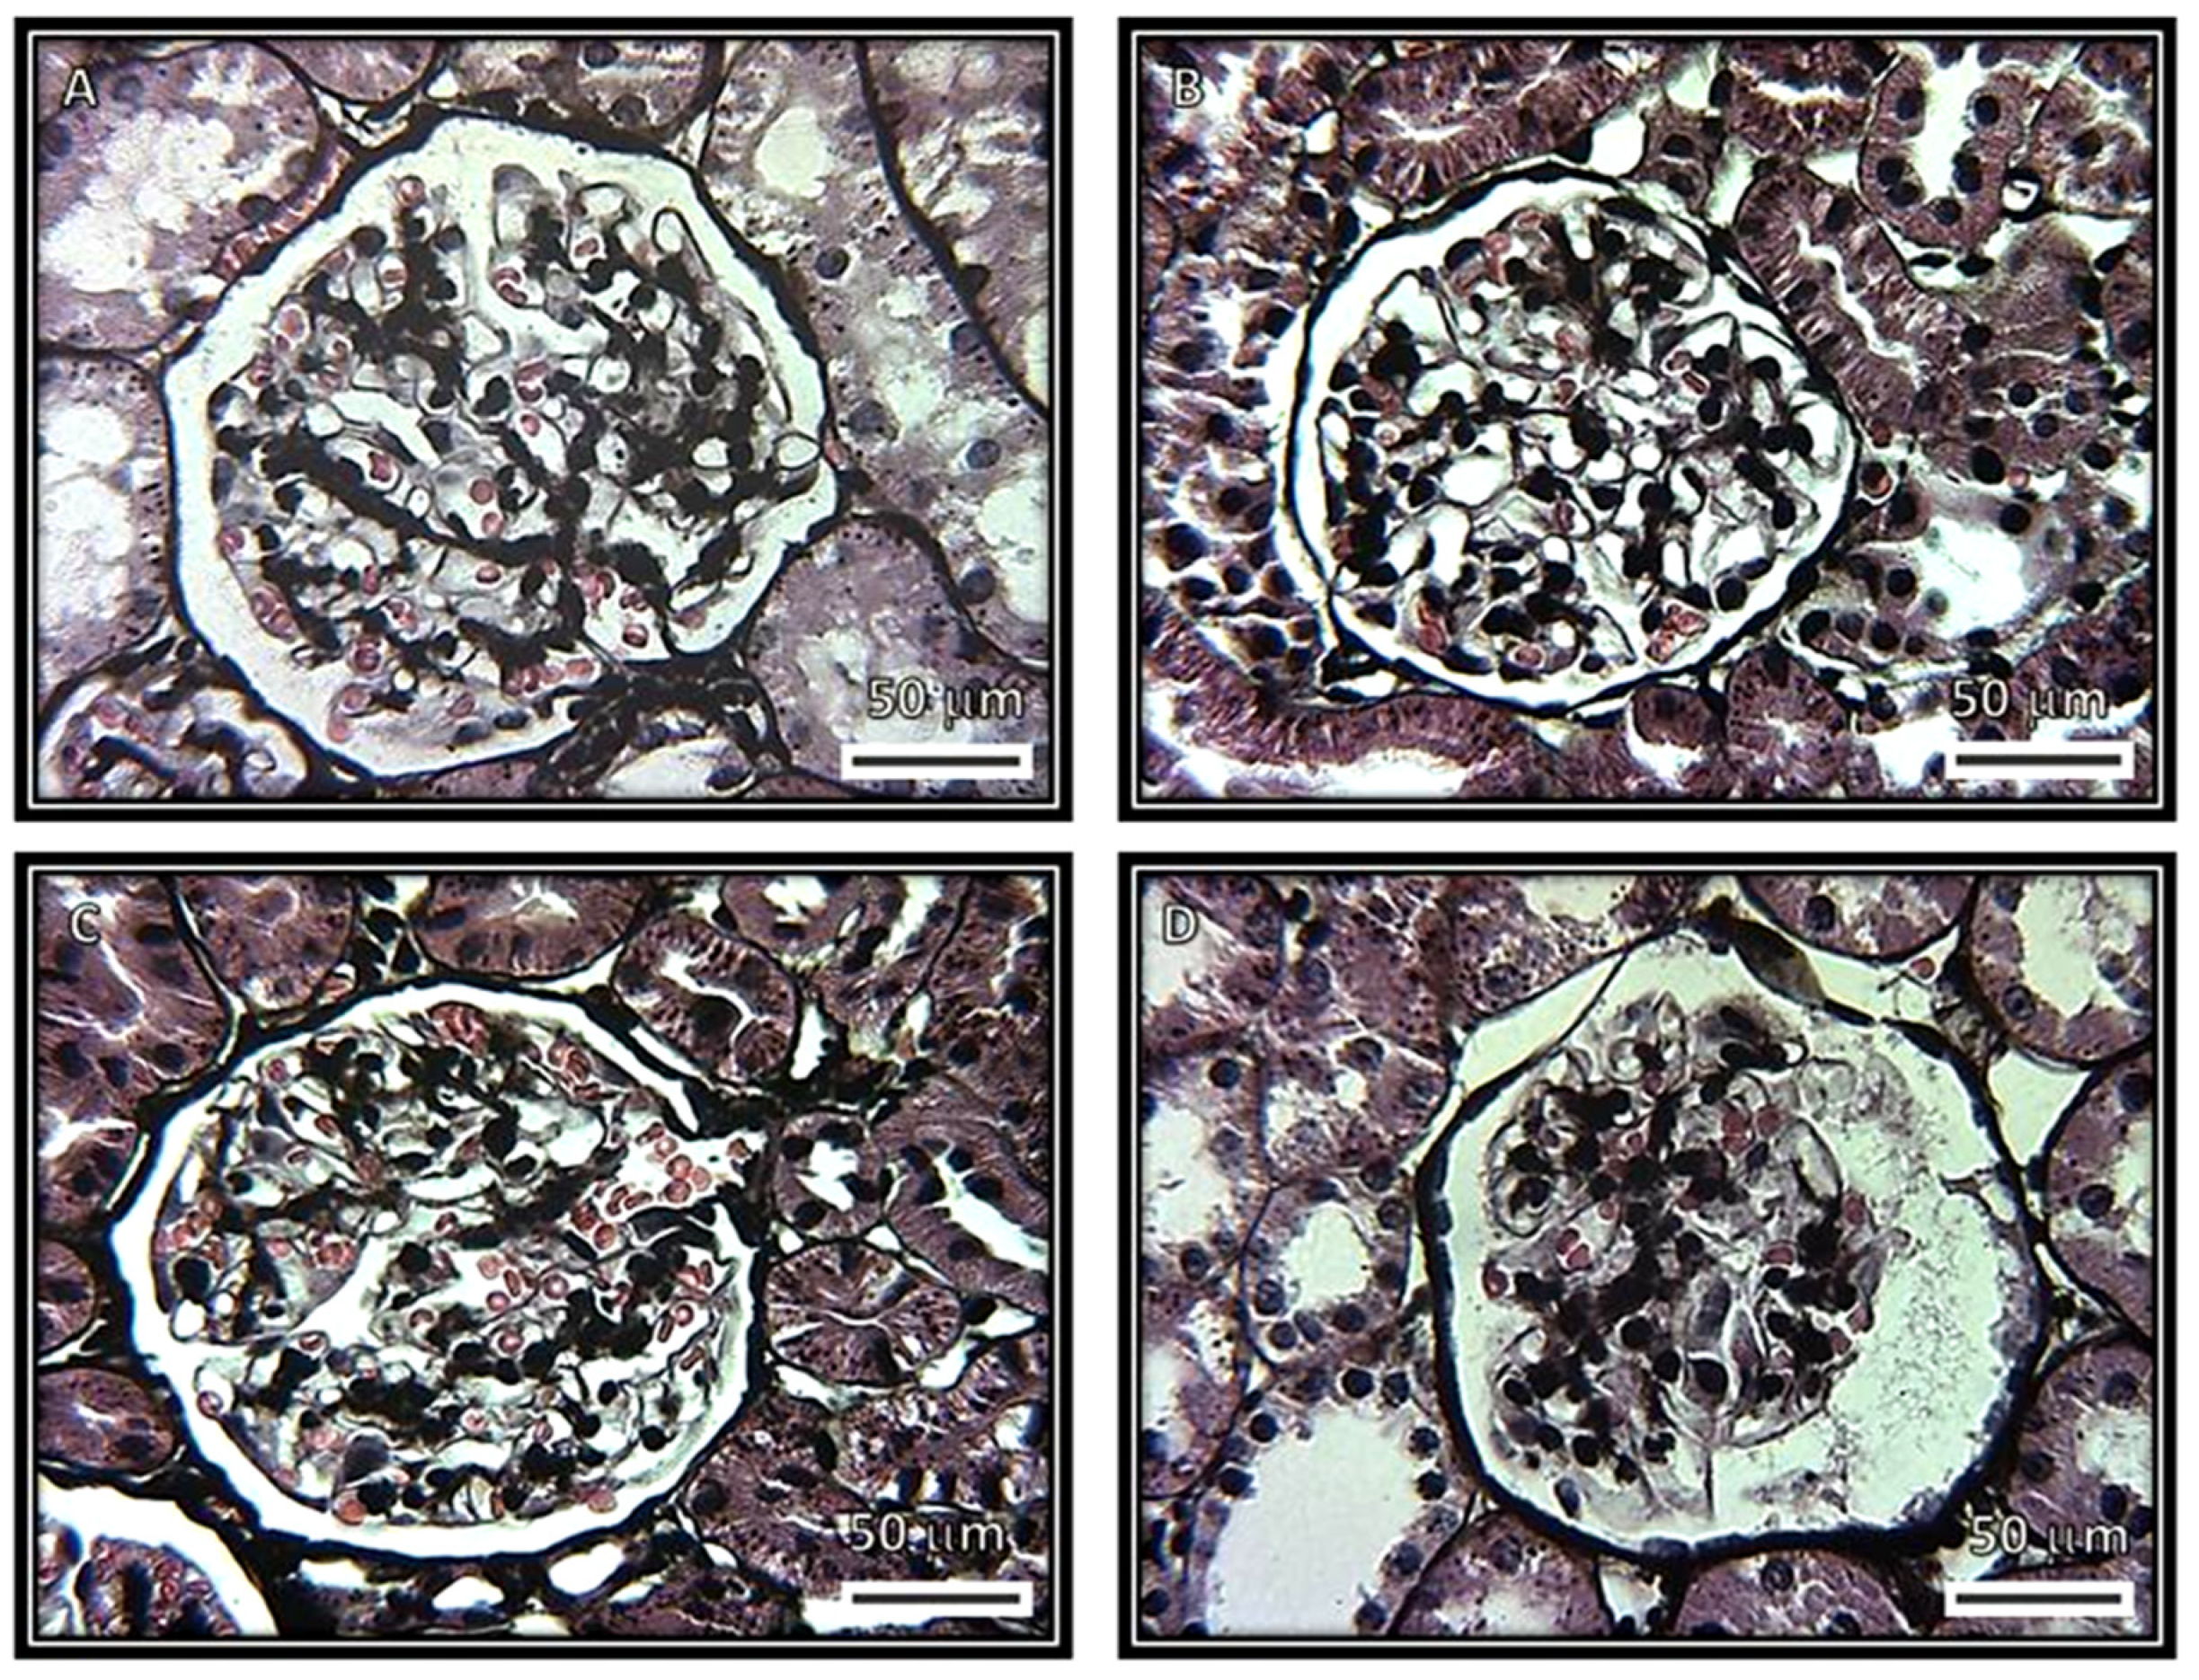

Figure 6 and Figure 7 show the representative immunolabeling for WT1 and the densitometric analysis in the glomeruli. The densitometric analysis of the immunolabeling showed a decrease for WT1 in the C (p = 0.03), SS (p = 0.007) and HS (p = 0.04) groups in comparison with the CG group.

Figure 8 and Figure 9 show the representative immunolabeling and densitometric analysis for TNFα in the glomeruli, respectively. The densitometric analysis of the immunolabeling showed a decrease for TNFα in the C (p = 0.001), SS (p = 0.006) and HS (p = 0.001) groups in comparison with the CG group.

Figure 10 and Figure 11 show the representative immunolabeling and densitometric analysis for 5-LOX in the glomeruli, respectively. The densitometric analysis of the immunolabeling showed a decrease for 5-LOX in the C (p = 0.02) and HS (p = 0.002) groups in comparison with the CG group.

Figure 6. Representative immunohistochemistry of rat renal cortex with the ripening marker WT1. The images show glomeruli from (A) control, (B) kidneys from rats that were injected with saline solution and (C) kidneys from rats that received serum from healthy subjects. The images in these three panels are positive for visceral cells. (D) Kidneys from rats that received serum from patients having collapsing glomerulopathy. The image is negative for visceral cells.

Figure 8. Immunohistochemistry of representative rat renal cortexes with the TNFα antibody. The images show glomeruli from (A) control, (B) kidneys from rats that were injected with saline solution and (C) kidneys from rats that received serum from healthy subjects. The images in these three panels show a negative stain. (D) Kidneys from rats that received serum from patients having collapsing glomerulopathy. In this panel, there is a positive stain.

Figure 10. Immunohistochemistry of representative rat renal cortexes for the 5-LOX antibody. The images show glomeruli from (A) control, (B) kidneys from rats that were injected with saline solution and (C) kidneys from rats that received serum from healthy subjects. The images in these three panels show negative stains. (D) Kidneys from rats that received serum from patients having collapsing glomerulopathy. In this panel, there is a positive stain.